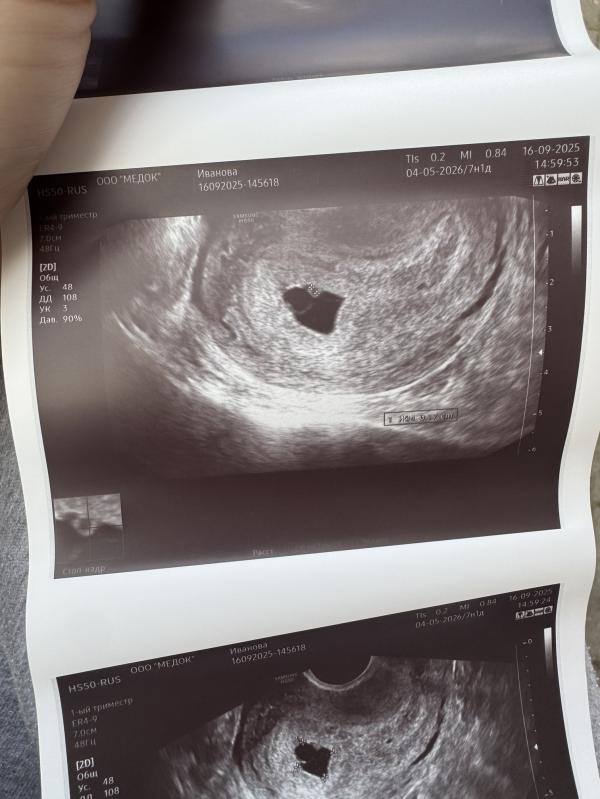

7нед 2д

Эмбрион так и не появился 😞

Появился уже даже хорион , но не эмбрион

Мешочек желточный ровный красивый

Контур хороший

А что внутри плодного яйца виднеется тогда?

Желточный мешок , и побольше колечко это хорион ( будущая плацента если не ошибаюсь )